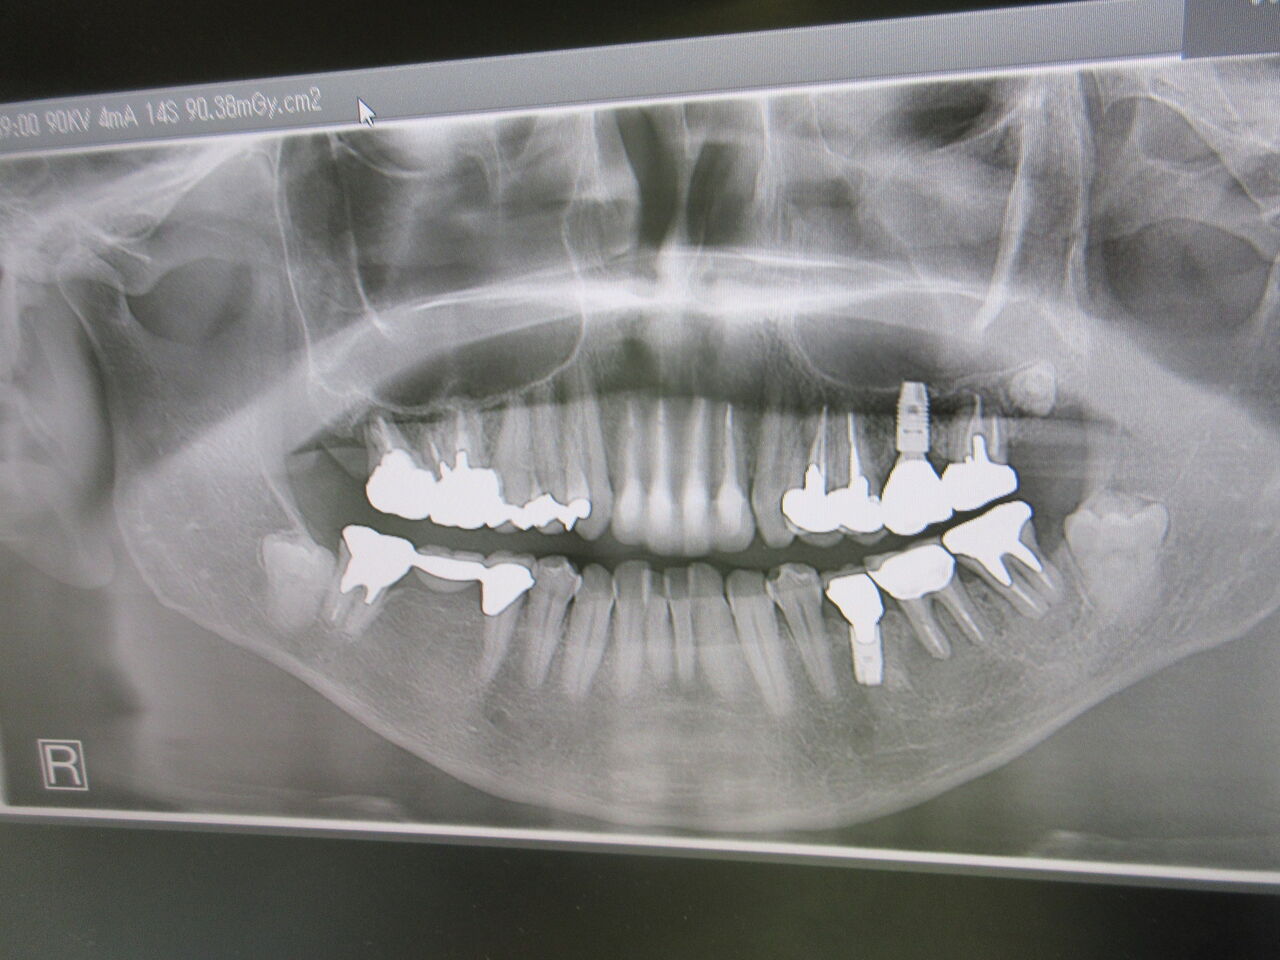

数年ぶりに来院された患者様でしたがパノラマレントゲンを撮ると下顎左側6番に骨透過像が見られます。CTで確認すると、かなり大きくおそらく手前のインプラントもだめにしてしまいます。

この場合は抜歯しかありません。定期的に来院して頂けたらかわっていたかも知れません。